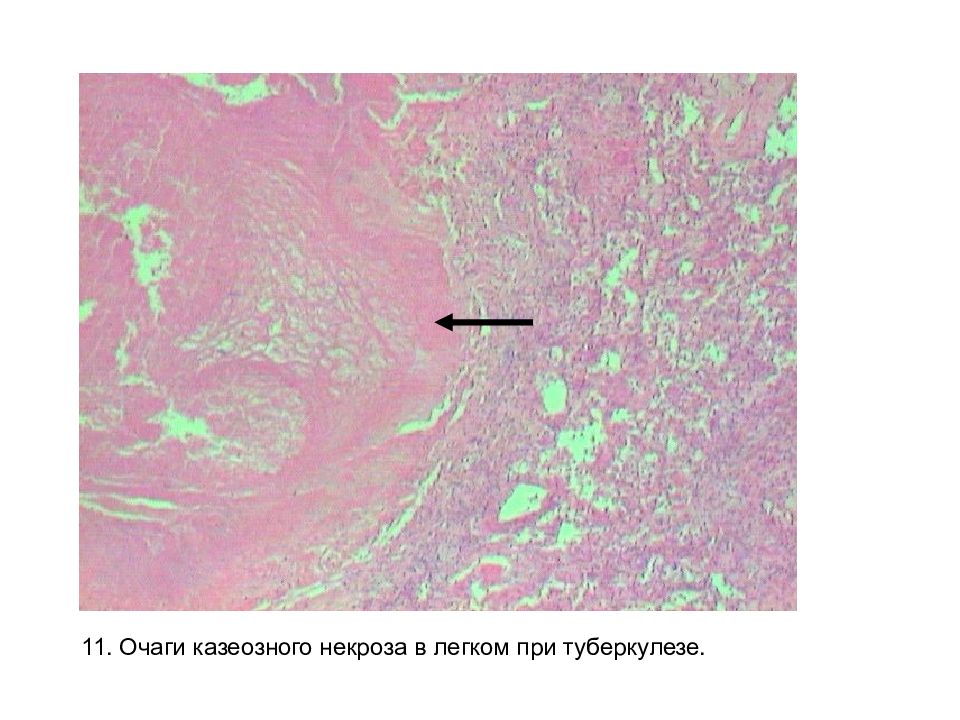

Микроскопический взгляд на мишитарный туберкулез легкого: фотодокументация

Раздел: Снимки-откровения